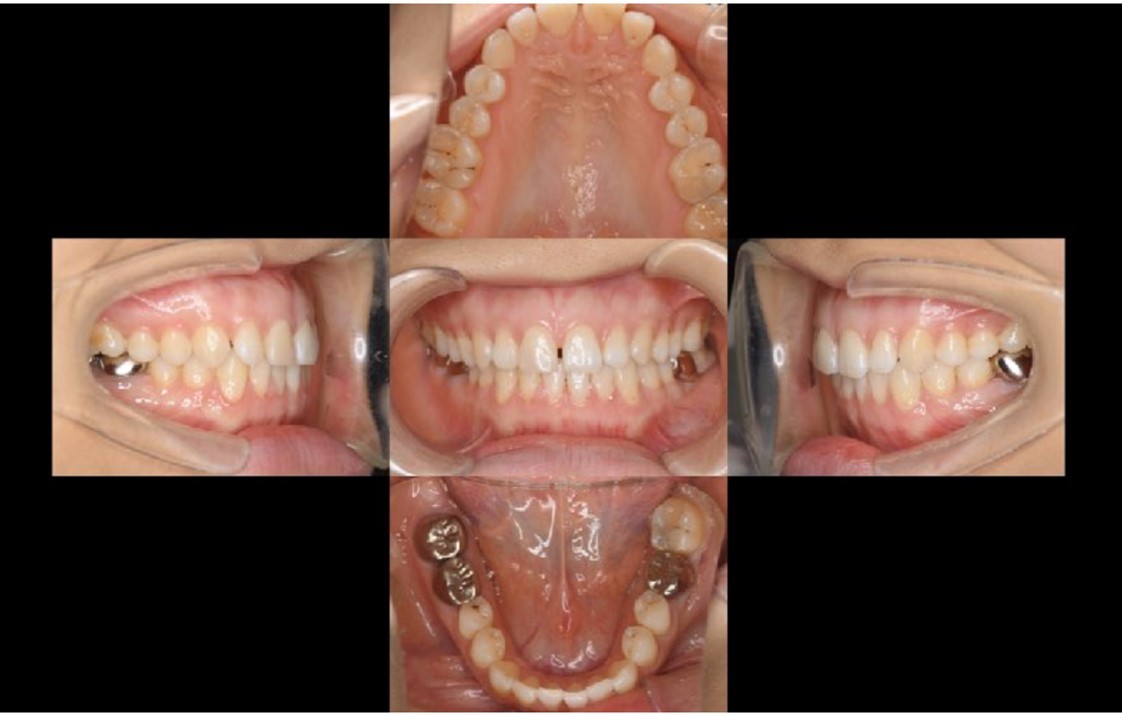

A 27-year-old female patient came to us with discomfort in the right lower jaw (Figure 1). Her primary symptoms were pain in the lower right tooth when biting and discomfort associated with not being able to chew well with the lower left single denture. The patient was married and had one young child, and previously received dental treatment in China, then had returned to Japan for childbirth and early childcare. The patient was a nonsmoker with moderate plaque control and medical history taking revealed no problems. In clinical and radiographic examinations, a root fracture was observed on tooth #46, which had been endodontic ally treated and restored with a full-cast metal crown. Periodontal probing revealed a pocket depth of 8 mm on the buccal center side of the tooth. No pain was detected with percussion and mobility of the tooth was normal. (Figure 1, Figure 2, Figure 3).

Bone regeneration was confirmed before and after grafting, after root filling, and after placement of the prosthesis, based on X-ray imaging results (Figure 8). There was no pathologic mobility or pain during mastication, and the tooth showed good function. The patient was very satisfied with the treatment results (Figure 9).

Following the operation, root canal treatment was performed as noted above. Functions including temporary crown occlusal contact and tooth mobility, as well as pocket depth were also checked. All examination results clearly indicated placement of a definitive prosthesis in the patient (Figure 13, Figure 14). At a follow-up examination one year after surgery, progress in this case was determined to be good (Figure 15).

The patient actively visited the clinic for maintenance and showed good compliance. Achievement of occlusal recovery using auto transplantation for prosthetic treatment of the missing right and left mandibular first molars fulfilled her wishes, and created a significant improvement in functionality, thus leading to improved quality of life.